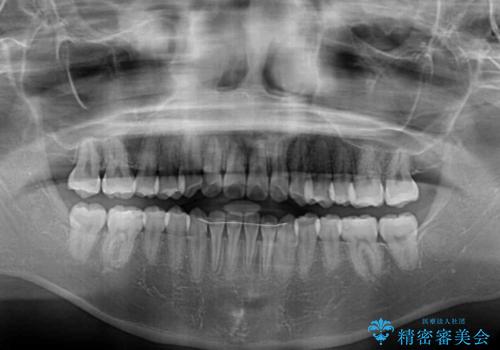

- 前歯のクロスバイトが気になり、インビザラインによる矯正治療を希望して来院された患者様です。

上顎側切歯(上の真ん中から2番目の歯)が舌側転位している場合、インビザラインでは仕上げきれないことが多く、更には無理して動かそうとすると歯髄壊死を起こすリスクが高いと言われています。

インビザラインで歯列を移動する前に、上顎前歯をワイヤー矯正で整え、その後上下歯列をインビザラインにて矯正治療を行うこととしました。

舌側転位している側切歯特有の、切縁の位置が不揃いであったり、根元が内側に引っ込んだ状態であったりという、インビザライン独特の仕上がりになることなく、きれいに整った歯列とすることができました。